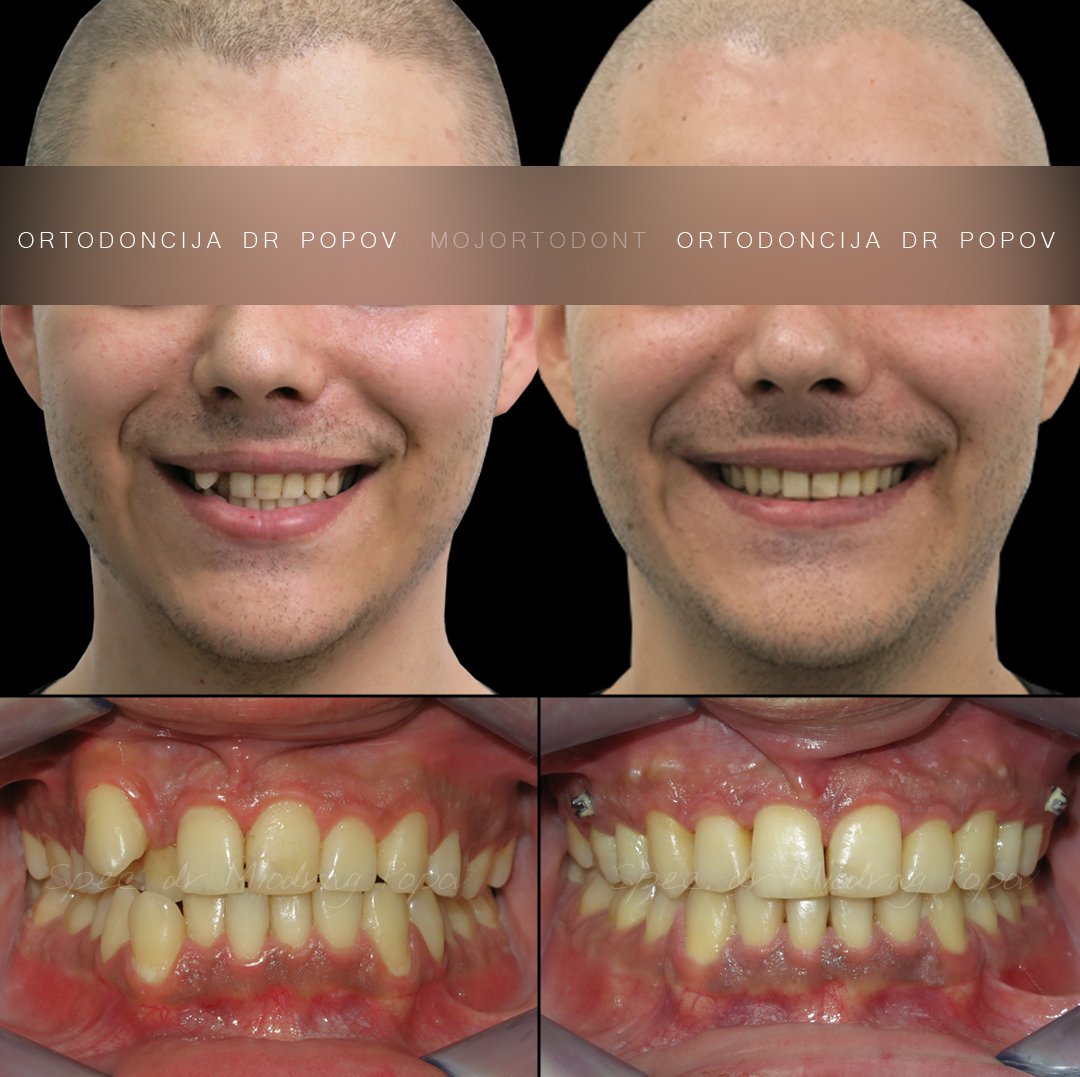

Uspešno završen slučaj ektopičnog očnjaka!

Ovaj pacijent se suočavao sa nekoliko ortodontskih izazova:

- Ektopičnim očnjakom

- Teskobom u zubnim nizovima, kao i

- Neslaganjem sredina gornje i donje vilice

Kroz precizno planiran i stručno vođen ortodontski tretman, uspeli smo da rešimo sve ove probleme.

Ektopični očnjak je uspečno postavljen na svoje mesto, teskoba je otklonjena, a sredine zubnih nizova su dovedene u savršen sklad.

Zadovoljstvo nam je što smo mogli da pomognemo pacijentu da povrati pravilan zagrižaj i lep, simetričan osmeh. Posle perioda stabilizacije sledi izbeljivanje zuba i korekcija oblika estetskim restauracijama.